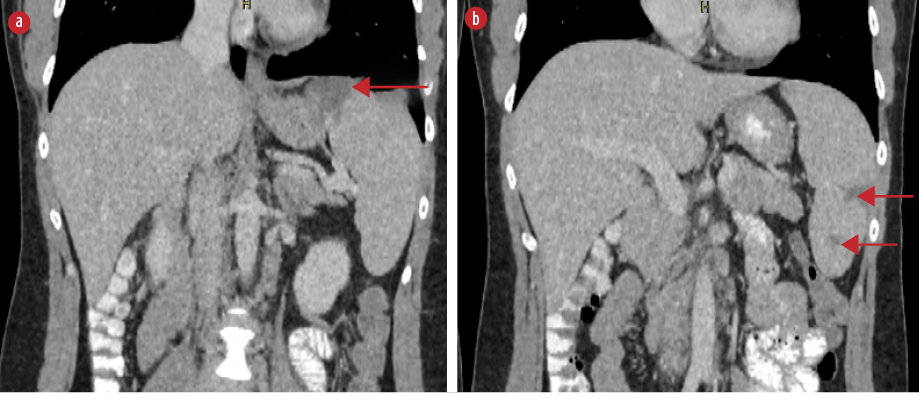

On the fifth day of hospitalization, the patient complained of new-onset left upper quadrant abdominal pain. Clinical examination revealed mild tenderness in the left upper quadrant and a palpable spleen. Computed tomography (CT) of the abdomen with intravenous contrast demonstrated multiple enlarged iliac lymph nodes, hepatomegaly (178 mm in the midclavicular line), and moderate splenomegaly (140 mm in the longitudinal axis). Multiple hypodense splenic lesions were visible without contrast enhancement, suggestive of splenic infarcts [Figures 1 and 2]. CT angiography of the abdomen showed no thrombi in the splenic vasculature. Hypercoagulability workup revealed mildly reduced protein S activity. Molecular testing for inherited thrombophilia (Factor V Leiden, Factor II-prothrombin, Factor XIII, MTHFR, and JAK2 V617 gene mutations) yielded negative results [Table 1]. Transesophageal echocardiography showed no evidence of thrombi, vegetation, or other abnormalities.

Figure 1: Axial contrast-enhanced CT scan demonstrating wedge-shaped hypodense splenic lesions without contrast enhancement indicative of splenic infarcts (red arrows), (a) located at the T10 level and at (b) the

L2 level.

Abdominal ultrasound is not recommended as the sole imaging modality because of its low sensitivity.6,9,14 The imaging modality of choice is contrast-enhanced CT, on which splenic infarcts commonly appear as wedge-shaped hypodense lesions without post-contrast enhancement after contrast administration.6,7 On magnetic resonance imaging, splenic infarcts are visualized as lesions with low signal intensity on both T1-weighted and T2-weighted images.9 In the present case, abnormal lesions suggestive of infarcts became evident on CT scan with intravenous contrast as wedge-shaped lesions without contrast enhancement.